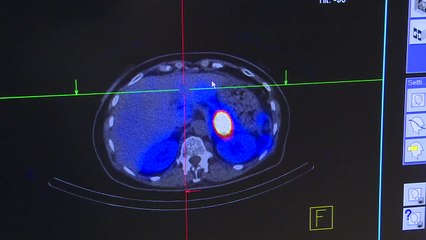

쿠바가 자체 생산한 약물로 자국의 코로나19 사망률을 크게 낮췄다고 발표했습니다. br br 쿠바 수반인 베르무데스 국가평의회 의장은 국영방송을 통해 "두 가지 약물을 활용해, 숨지거나 중태에 빠질 뻔한 확진자 80를 살려냈다"고 밝혔습니다. br br 이 가운데 하나는 '이톨리주맙'으로, 주로 건선 치료에 사용되는 모노클로날 항체 약물입니다. br br 다른 약물은 쿠바의 제약업체가 류머티즘 관절염 치료제로 사용하고자 2상 임상시험을 진행 중인 펩타이드 약물입니다. br br 이에 대해 전문가들은 해당 약물이 코로나19 치료에 안전하고 효과적인지 검증하려면 대규모 대조군 시험이 필요하다고 지적했습니다. br br 월드오미터의 통계를 보면 오늘 오후 1시 기준 쿠바의 누적 확진자는 천9백여 명, 사망자는 81명으로, 치사율은 4.2 정도 됩니다.br br ▶ 기사 원문 : ▶ 제보 안내 : , 모바일앱, social@ytn.co.